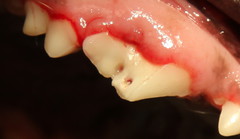

Eigentlich sollte bei diesem Hund eine Zahnprophylaxe durchgeführt werden. Bei der jährlichen Routineuntersuchung war vermehrte Zahnsteinbildung - besonders auf der rechten Seite - aufgefallen. Nach gründlicher Reinigung in Narkose fiel uns am Reißzahn im rechten Oberkiefer ein kleines Loch auf, das sich unter dem Zahnstein versteckt hatte. Im Röntgenbild erkennt man, dass die Wurzel angegriffen ist: durch das Loch konnten Keime aus der Maulhöhle in den Wurzelkanal eindringen. Die kleinen Pfeile weisen auf den entzündeten Knochen am Zahnfach. Dies ist die Erklärung für die vermehrte Zahnsteinbildung auf der rechten Seite: die Entzündung verursacht Zahnschmerzen und der Hund vermeidet es, auf dieser Seite zu kauen. Der entzündete Zahn wurde gezogen - die Entzündung heilt unter Antibiose und Schmerztherapie nach ein paar Tagen ab.

Loch im Zahn Die Sonde bleibt im Loch stecken